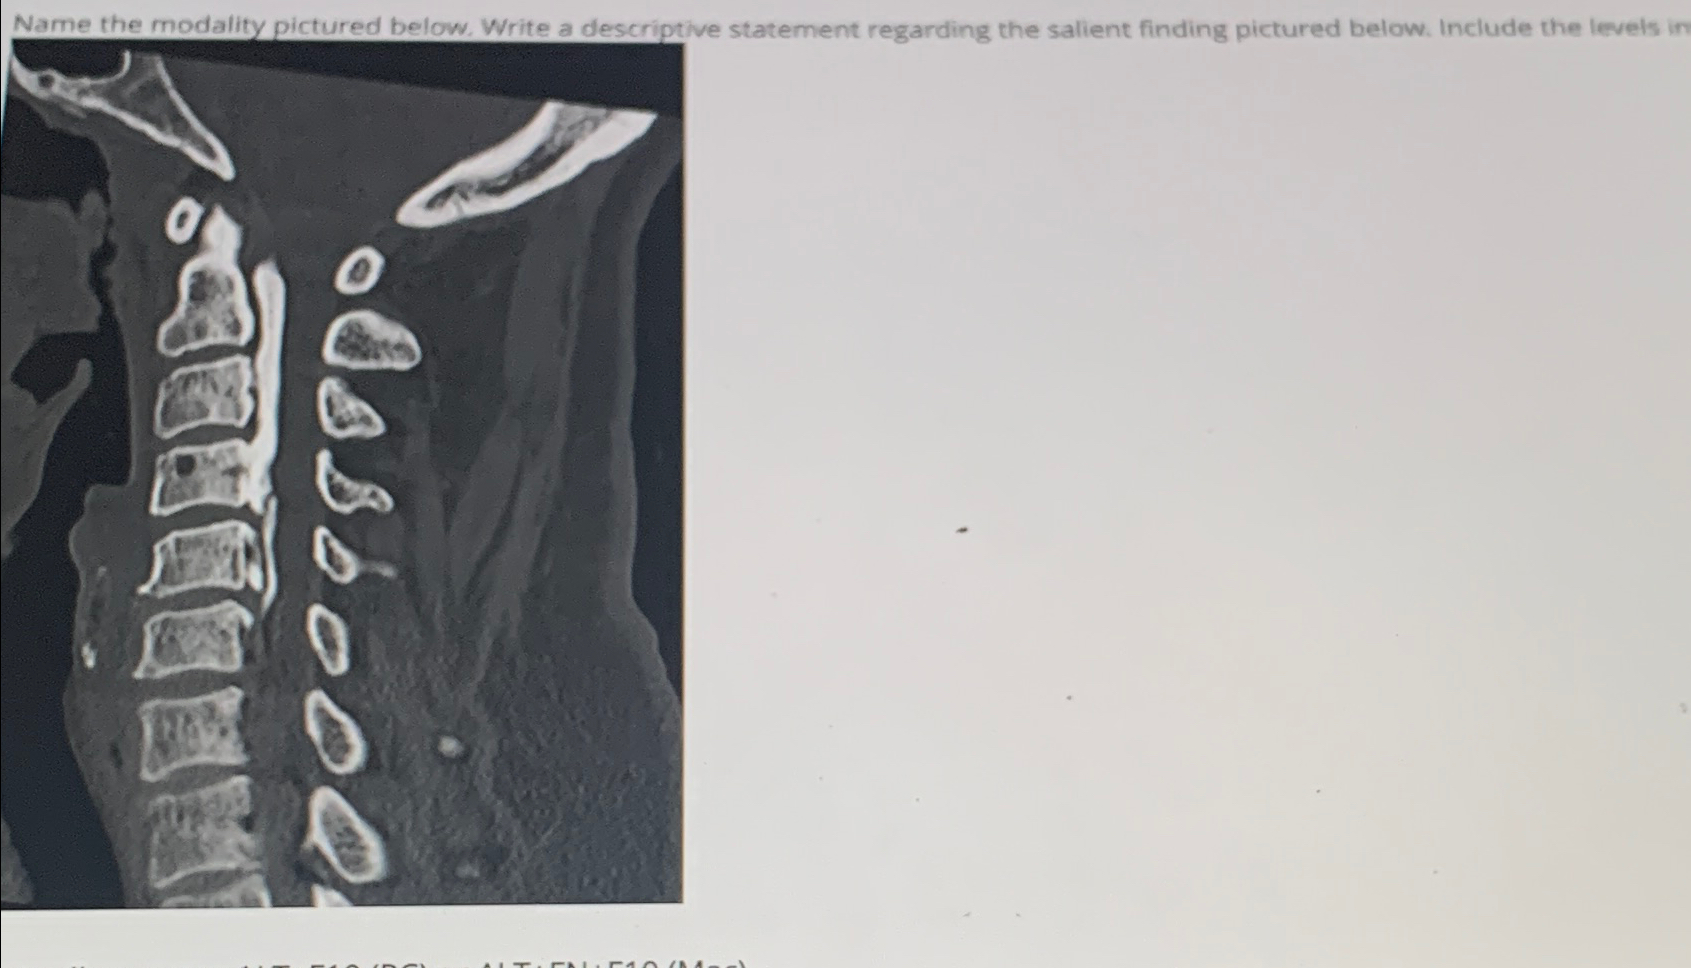

Question: Name the modality pictured below. Write a descriptive statement regarding the salient finding pictured below. Include the levels in

Name the modality pictured below. Write a descriptive statement regarding the salient finding pictured below. Include the levels in